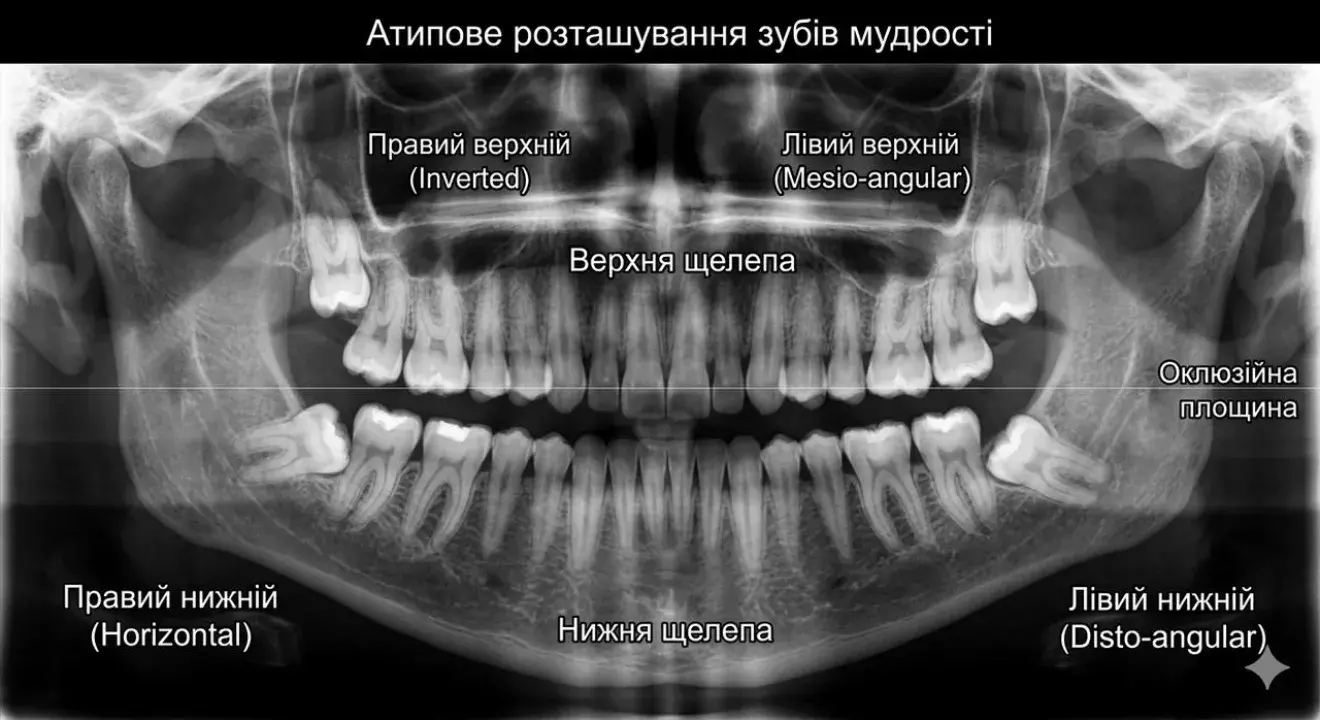

Діагностика та планування

Все починається з детального вивчення знімка. Хірург оцінює положення коренів відносно нервів та сусідніх зубів